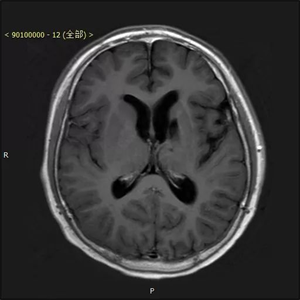

患者术后资料(下图)